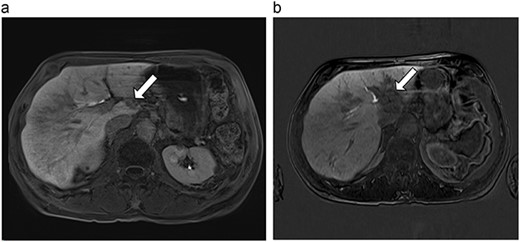

| 1 (3a,b) | 61, F | Colon adenocarcinoma | 6-month FOLFOX | 1 | Laparoscopic microwave ablation | 6 | 40.4 | 34.4 | 10 | No |

(a) Pre-ablation MRI demonstrates 6 mm lesion in caudate lobe of liver. (b) Post-ablation MRI (18 days postoperatively) demonstrates 40.4 mm complete ablation site in caudate lobe of liver.